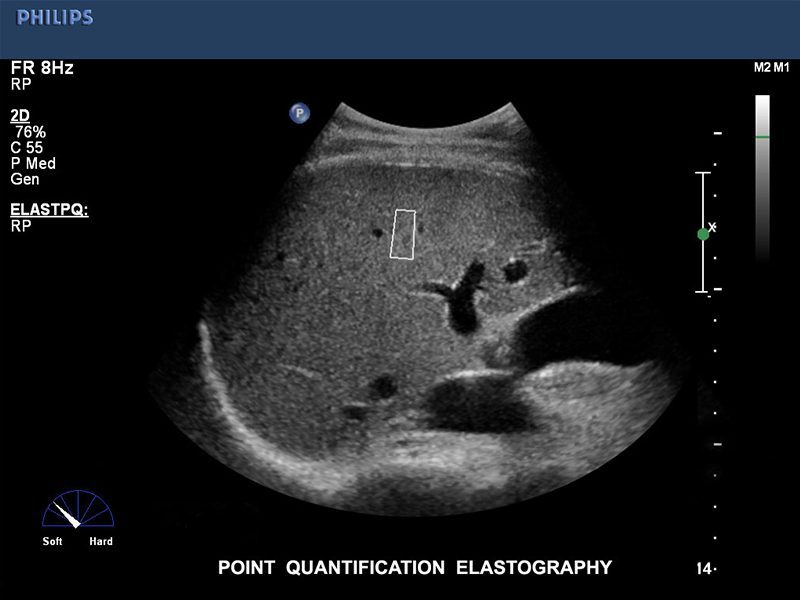

El ultrasonido iU22 xMatrix es un sistema que provee imágenes nítidas de alta resolución, y calidad única en 2D, 3D Y 4D de un mismo transductor. Provee una perspectiva clara durante las biopsias y ablaciones. El equipo tiene la capacidad de realizar el estudio de elastografía mamaria.

Elastografía por ultrasonido